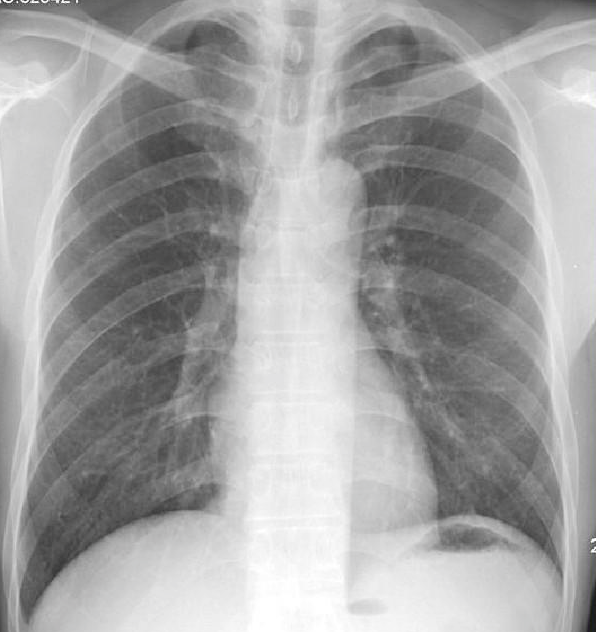

病例2:胸部摄片未见明显异常,

但CT扫描发现右肺结节,

术后病理检查:原位腺癌

CT检查,通俗来讲就是把人体结构扫描成数层断层图像,是剖面图,互补重叠干扰,其中薄层扫描可以发现3mm以下的病变,这是摄片(DR)不能实现的。这样我们就能发现早期病变,尤其是恶性肿瘤,可以做到早期切除,彻底治愈。